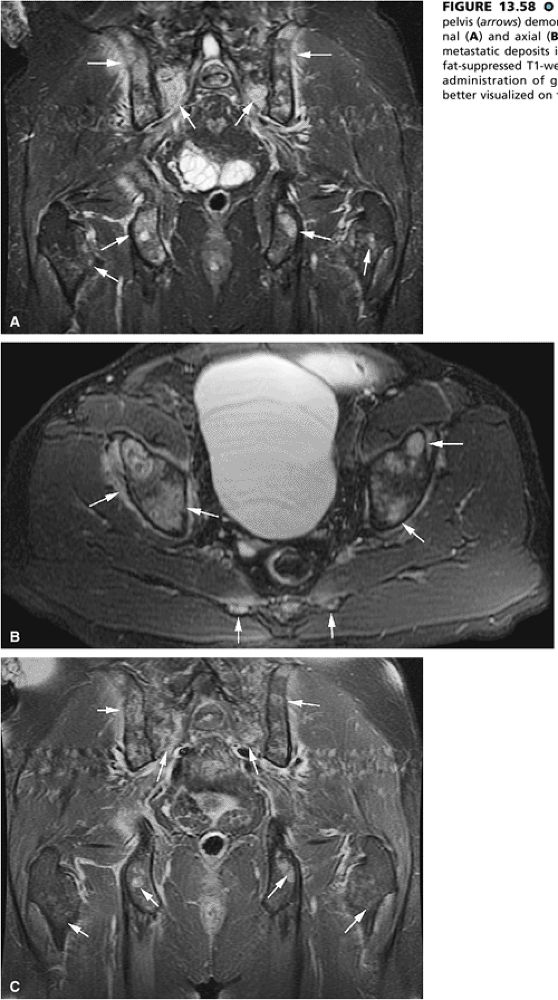

FIGURE 13.58 ● Colon carcinoma metastatic to the pelvis (arrows) demonstrates high signal intensity on coronal (A) and axial (B) STIR images. (C) Enhancement of metastatic deposits is noted on a corresponding coronal fat-suppressed T1-weighted image following intravenous administration of gadolinium. Metastatic deposits are better visualized on the STIR sequence.